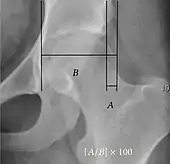

- Reimer's migration index (MI), also called the femoral extrusion index,[3] is calculated if hip dysplasia is detected. It can be used to indicate hip dislocation. It is the horizontal distance (parallel to the Hilgenreiner Line) between the Perkin line and the lateral border of the ossification center of the femoral head, divided by the horizontal width of the ossification center. The migration index is normally less than 33% by most sources,[9] but 25% and 30% has also been suggested.[10]

| Acetabular depth ratio | ![]() |

Deepness of acetabulum. | >250

|

| Reimer's migration index[9] | ![]() |

The percentage of the femoral head that lies outside of the acetabular roof. It is also called the femoral extrusion index. | <25% |